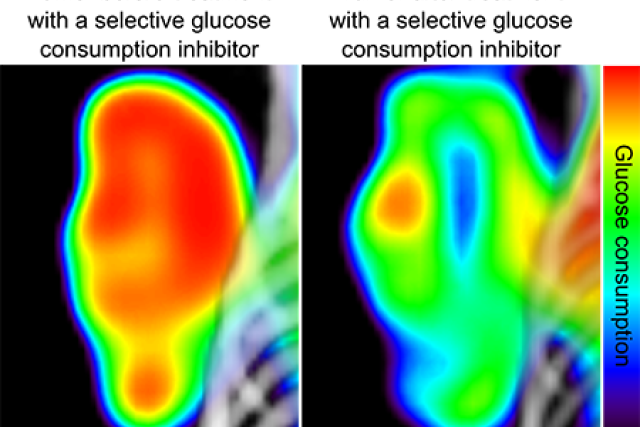

Cancer metabolism glucose consumption captured by heat scan.

Before and after: The tumor pictured on the left has metabolized a high amount of glucose, the sugar it needs to grow. The same tumor is shown on the right after it has been treated with a molecule that prevents it from consuming glucose.